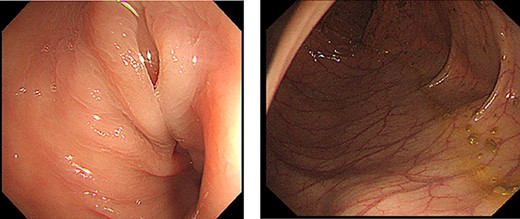

The sigmoid colon was elongated, and a scar was detected near the SD junction, which appeared to be a site of repeated torsion (Fig. 4). Dilation of the sigmoid colon revealed no inflammation on the serosal surface. The laparoscopic procedure was completed after confirming that the sigmoid colon was sufficiently elevated to the left lower abdomen. A 4-cm cross incision was made at the opposite of McBurney’s point, and the sigmoid colon was raised outside the wound (Fig. 5). The intestine was considered to be sufficiently decompressed to allow anastomosis. The intestinal tract was separated, and anastomotic reconstruction was performed using functional end-to-end anastomosis. The operation duration was 89 min, and the bleeding amount was 5 ml.

Surgical findings. Sigmoid colon was elongated and there was scar near the SD junction.

Method of Sharon operation. Sigmoid colon was raised outside the wound at the opposite of Mc Burney’s point.